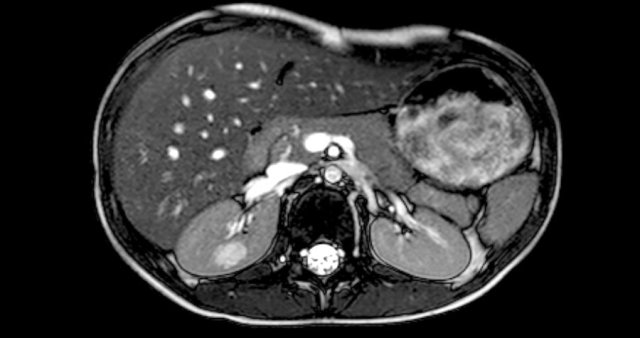

here an one and a half year old girl with a palpable tumor in the left abdomen.

Ultrasound showed a large tumor composed of innumerable cysts, originating from the left kidney.

On a T2 weighted coronal image the cysts are well displayed.

The remainder of the left kidney is at the caudal side of the tumor.

On pathology a cystic partially differentiated nephroblastoma was diagnosed.